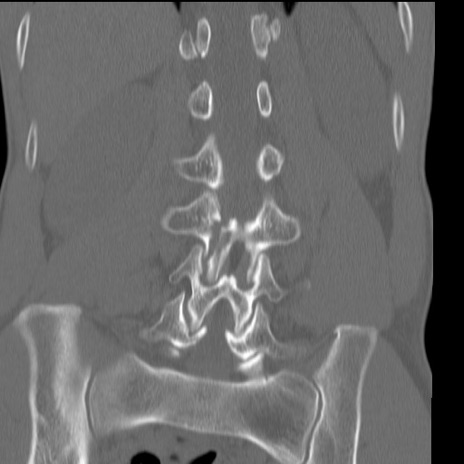

症例3 腰椎CT(冠状断像)

腰椎CT